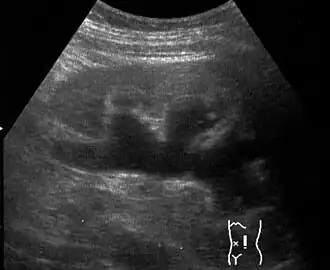

![]() Ecografía renal en la que se observa la existencia de hidronefrosis. | ||